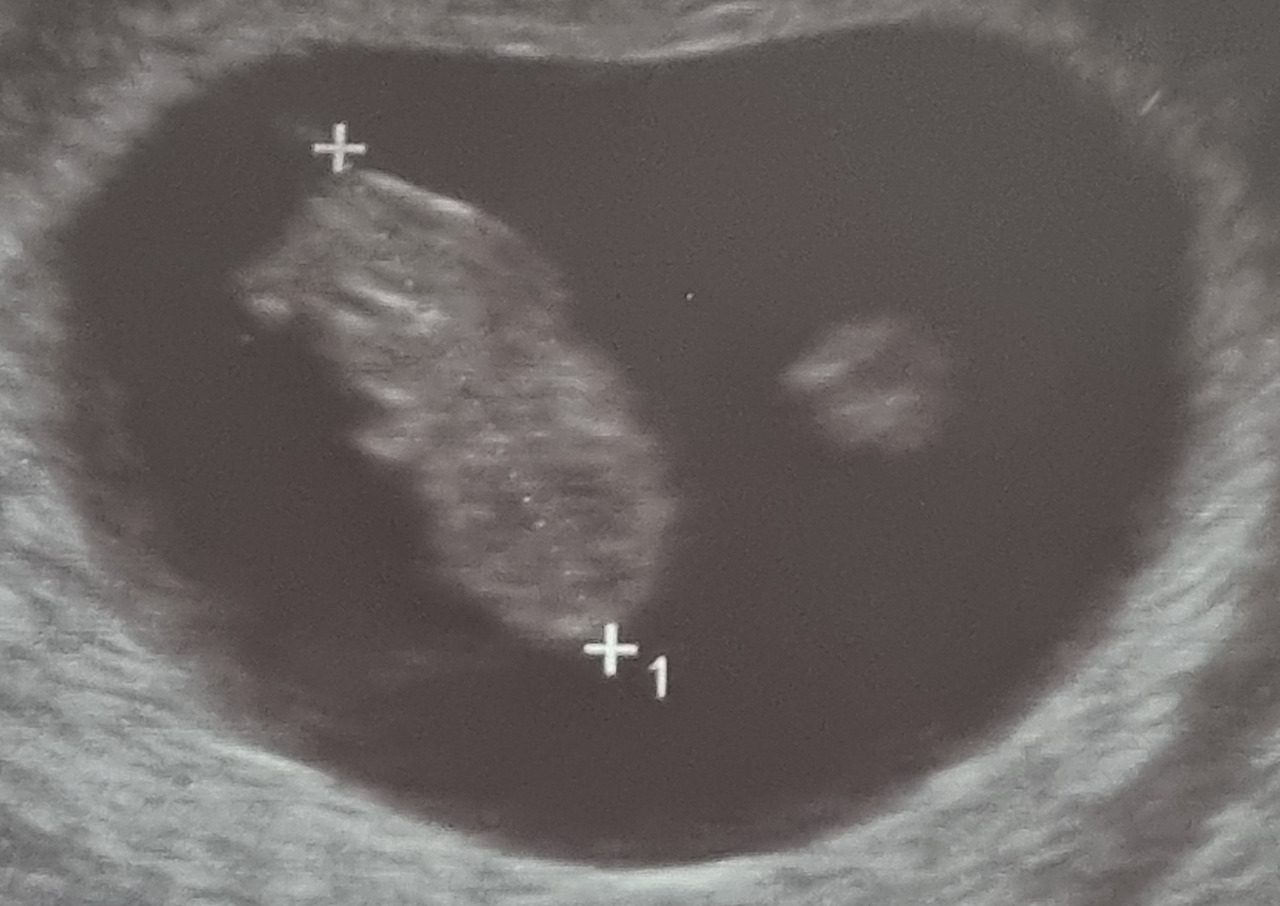

다행히도 좋은 느낌은 그대로 좋은 소식으로 이어졌다. 난생처음 점점 뚜렷해지는 임테기 두 줄을 확인할 수 있었고, 오늘로 임신 9주 2일 차인 지금, 8주 5일 차에 초음파 상으로 확인한 대로 나에게 찾아온 아가는 건강하게 자라나고 있다. 이제 배아에서 태아로, 점점 사람 모양을 갖추면서 말이다.

8주 5일차.jpg